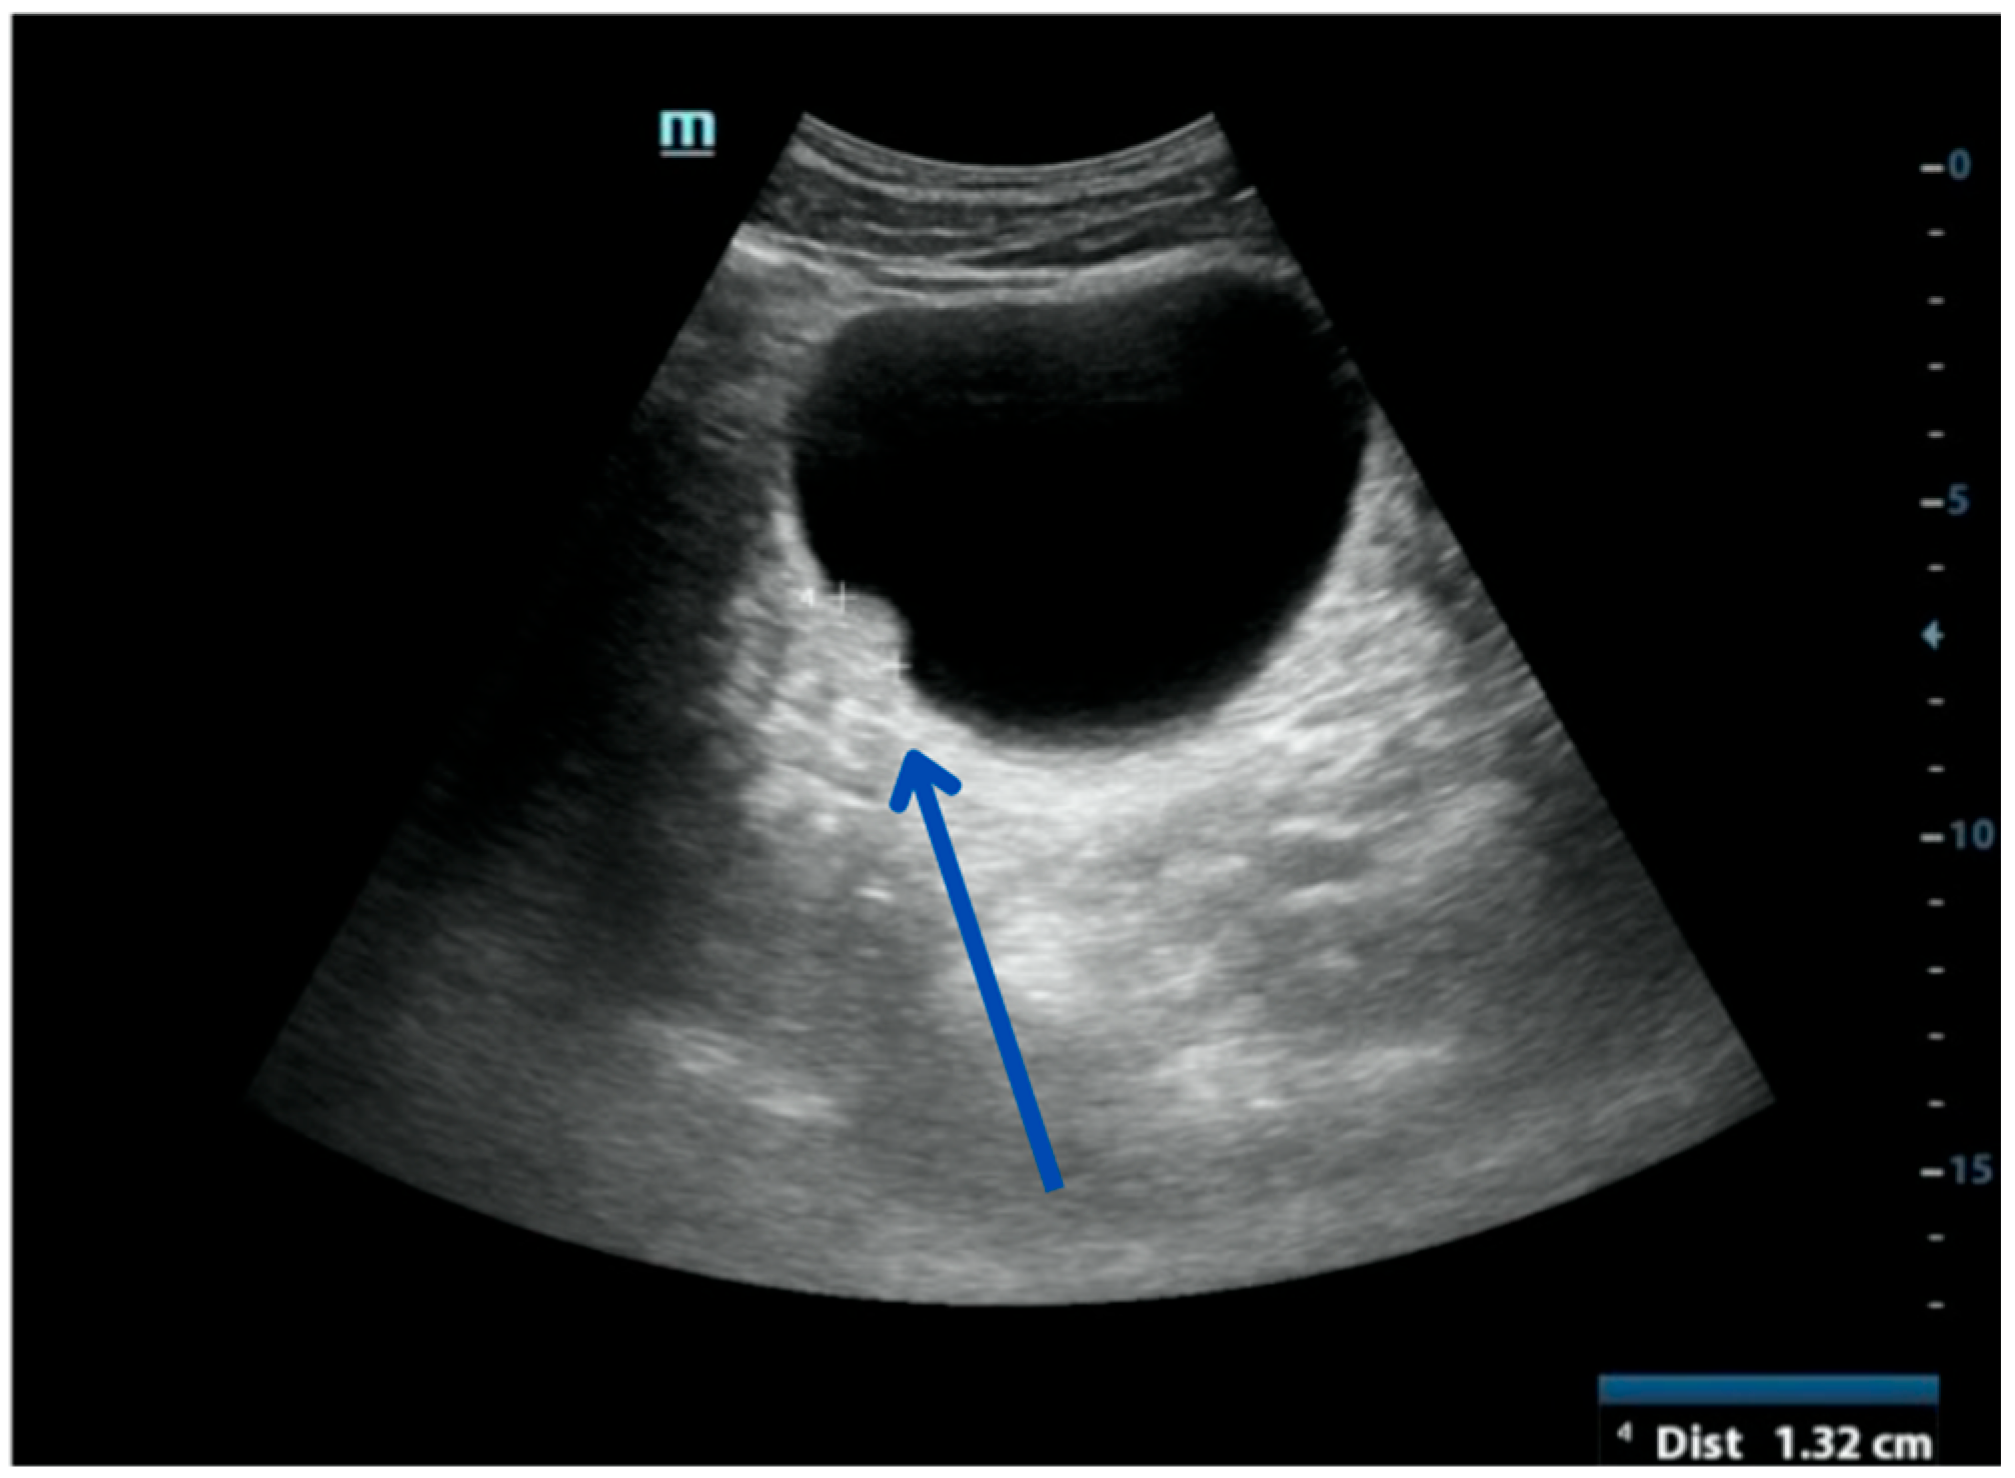

| US | Fatty composition showcasing homogenous, hyperechogenic lesion with endophytic growth.(Figure 7) | -Echogenicity could be very similar to the fat around the bladder, as observed by Paniagua et al., potentially mimicking an extravesical lesion pushing into the bladder (Figure 5) [22]. -In Ukita S et al.’s case of a retropelvic lipoma, TVUS revealed an echogenic mass in the right adnexal region, suggesting a mature ovarian cystic teratoma congaing fat. MRI and surgery were required for confirmation and treatment [16]. |